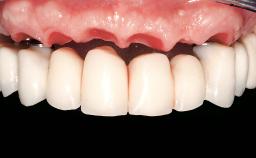

Conventional Loading of Eight Implants in the Maxilla and Final Restoration with a Full-Arch Gold-Ceramic FDP

Prosthesis Type | FDP |